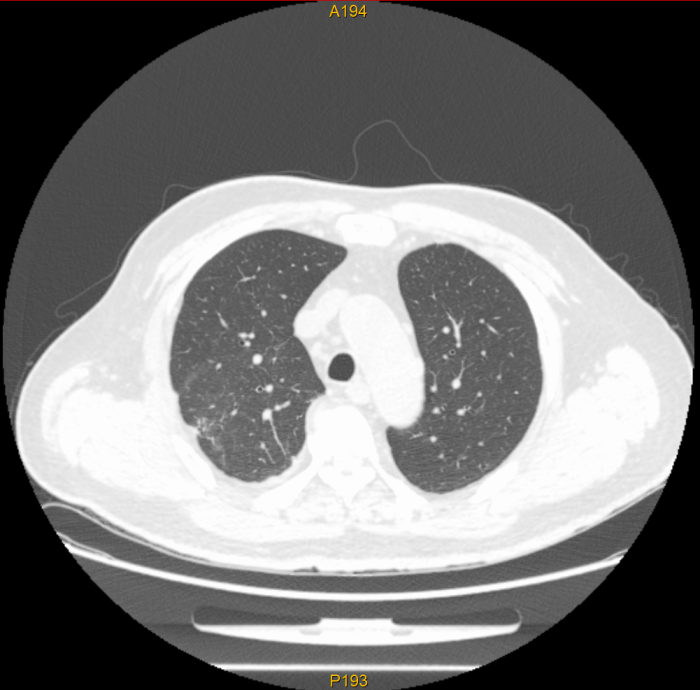

近日,我院肿瘤放射治疗科应用体部立体定向放疗(SBRT)技术,为一名胆管癌肺转移患者实施了精准放射治疗。通过制定规范的放射治疗计划,肺部两个转移病灶在接受SBRT治疗后基本消失,复查影像显示肿瘤已得到良好控制,彰显了精准放疗技术在肿瘤治疗中的独特优势。

该患者为胆管癌术后出现肺转移,两个转移病灶分别位于右肺上叶后段(大小26*25mm)及右肺下叶前基底段(大小28*30mm)。此前,患者已接受肝动脉化疗灌注(HACI)及多疗程全身化疗,但肺部病灶仍有增大趋势,治疗一度陷入困境。

治疗过程非常顺利,患者无明显不适。治疗结束后复查,两个肺部转移病灶已基本消失,显示出SBRT在局部肿瘤控制方面的绝对优势。这一结果不仅为患者带来了新的希望,也再次印证了精准放疗在肿瘤综合治疗中的重要地位。